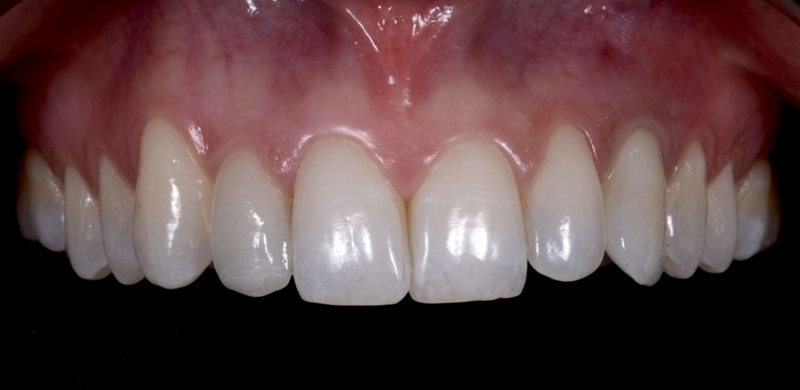

患者和我们的团队对最终结果在健康、美观和功能方面都非常满意。即使详细分析,也很难识别出最终的修复体(图63)。

Fig. 63: Frontal view of the final result.